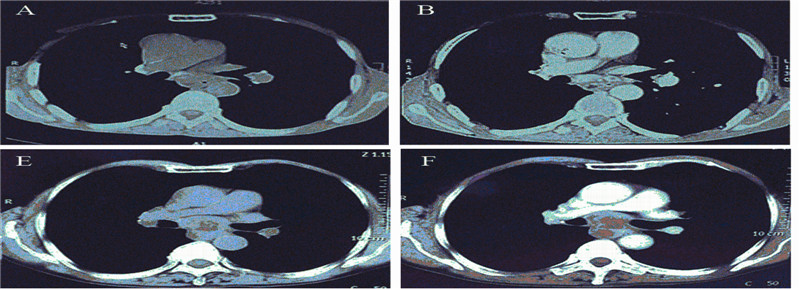

2.2 CT扫描淋巴结转移的特点单因素分析:隆突下淋巴结转移与淋巴结的短长径之比[(0.72±0.26):1 vs.(0.83±0.19):1,χ2=13.678,P<0.001]具有相关性(rs=-0.448),且与淋巴结的短径[(12.11±9.31) mm vs.(10.95±4.03) mm,χ2=9.718,P=0.002)]具有相关性(rs=0.378)。隆突下淋巴结转移[(57.25±45.00) Hu vs.(69.39±49.81) Hu,χ2=0.546,P>0.05]与CT扫描增强前后密度差无关,见表 1、图 1。

| A:plain scan,CT value:45.56Hu;B:enhanced scan,CT value:100.68Hu;A-B:CT showed obvious subcarinal lymph node enlargement,the ratioof length-short diameter was more than 2:1,considered as transfer,confirmed as transfer pathologically;C:plain scan,CT value:41.04Hu;D:enhanced scan,CT value:49.88Hu;C-D:CT showed no obvious subcarinal lymph node enlargement,the ratio of length-short diameter was more than2:1,considered as transfer,confirmed as no transfer pathologically;E:plain scan,CT value:45.40Hu;F:enhanced scan,CT value:76.88Hu;E-F:subcarinal lymph node ring-enhancement and central necrosis,the size was 3.7cm×3.5cm,confirmed as transfer pathologically;G:plain scan,CTvalue:38.55Hu;H:enhanced?scan,CT value:75.35Hu;G-H:CT showed moderate subcarinal lymph node enlargement,the size was 2.7cm×1.4cm,considered as transfer,confirmed as no transfer pathologically 图 1 胸中下段食管鳞癌隆突下淋巴结转移CT扫描特征 Figure 1 CT scanning characteristics of subcarinal lymph node metastasis in middle and lower segment of thoracic esophageal squamous carcinoma |

对照术后病理,本研究对隆突下淋巴结转移的CT扫描特征的一致性进行分析,见表 2。其与术后病理的一致率为8 9.6 6%,特异性为94.44%,敏感度为66.67%,误诊率为5.56%,漏诊率为33.33%,阳性预测值为71.43%,阴性预测值为93.15%。经一致性检验,Kappa=0.628,P<0.001,两者比较具有统计学意义。